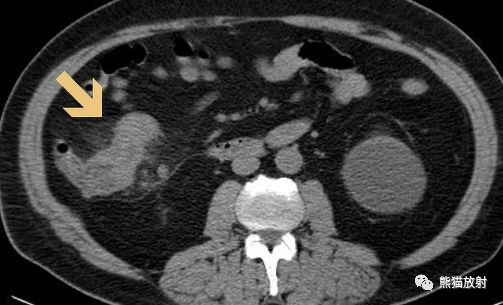

在CT图像上同样可以有苹果核征的表现。

横结肠癌CT表现及大体病理: